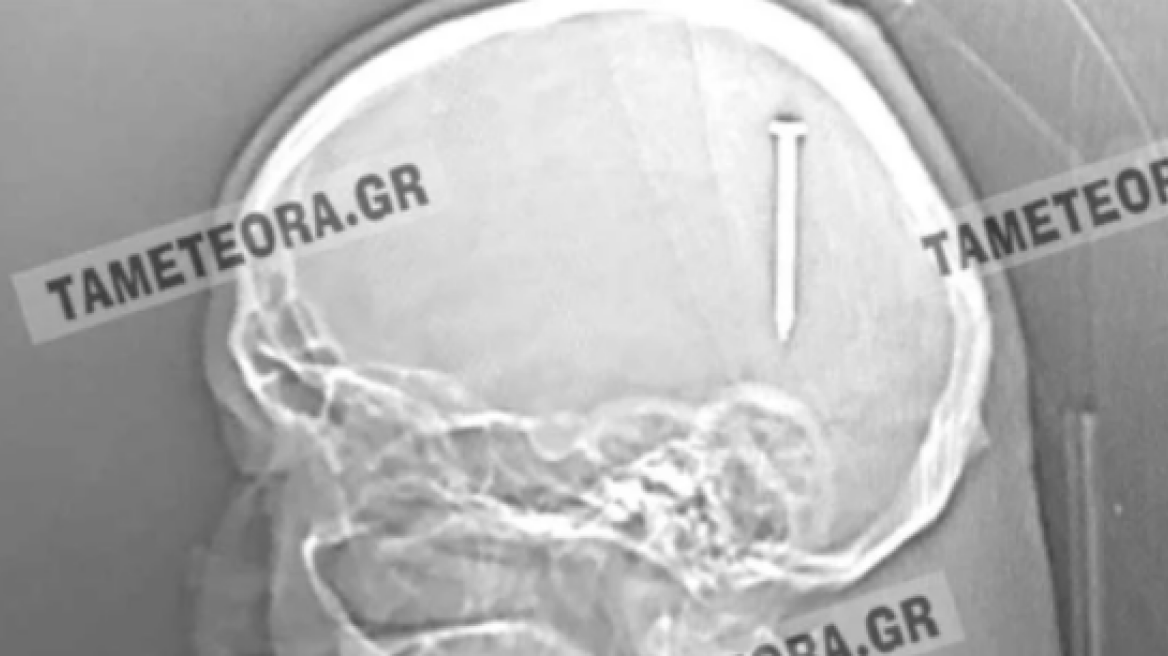

Από θαύμα ζει ένας κάτοικος της Καλαμπάκας, καθώς βρέθηκε ξαφνικά με ένα καρφί 5 εκατοστών σφηνωμένο στο κεφάλι του.

Σύμφωνα με το tameteora.gr, εκτός από το αρχικό τράνταγμα που ένιωσε κατά τη διάρκεια εργασιών που έκανε, ο άνδρας δεν ένιωσε πόνο, ούτε είχε κάποιο άλλο σύμπτωμα.

Ο άνδρας μεταφέρθηκε αρχικά στο Κέντρο Υγείας Καλαμπάκας, στη συνέχεια στο Γενικό Νοσοκομείο Τρικάλων και από εκεί στο Πανεπιστημιακό Νοσοκομείο Λάρισας, όπου υποβλήθηκε σε επέμβαση και του αφαιρέθηκε το καρφί με επιτυχία.

Ο άνδρας αναρρώνει υπό την παρακολούθηση των γιατρών. Εκτιμάται ότι δεν διατρέχει κανέναν κίνδυνο η υγεία του. Πρόκειται πραγματικά για ένα σπάνιο περιστατικό, καθώς αν το καρφί βρισκόταν ελάχιστα χιλιοστά από το σημείο που σφηνώθηκε, θα ήταν πολύ επικίνδυνο.